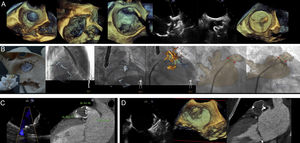

The LAA closure procedure is usually guided with TEE (Figure 2A): LAA en-face 3D-view; 3D-guided transseptal puncture; sheath inside LAA; 2-dimensional-orthogonal views (45° to monitor the circumflex artery and 135° to supervise the deployment depth); and device prior to being released. Some new imaging techniques are helpful complements (Figure 2B). Through the use of 3D-printed models, the LAA can be assessed easily, and it is also possible to assay deployment. Likewise, TEE or CT fusion imaging improves spatial comprehension.

According to imaging follow-up, residual leak (Figure 2C) can be difficult to identify with TEE. On CT, it appears as LAA contrast enhancement distal to the closure device. Thrombus (Figure 2D) can be identified on the external device surface on TEE as an irregular hyperechogenic structure, or as a low attenuation defect on CT.